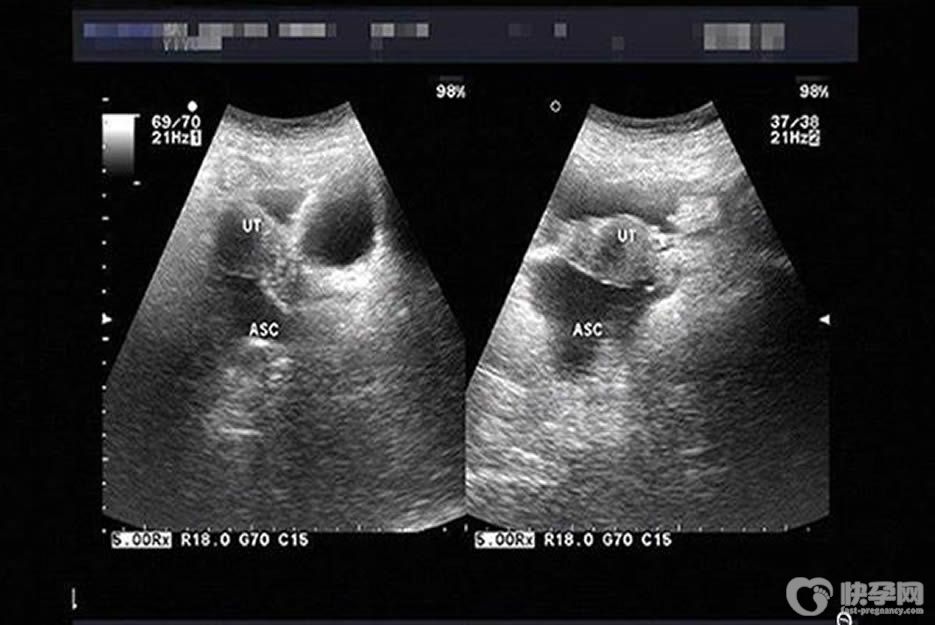

一般情况下,积液不超过10mm,属于正常,也就是生理性盆腔积液。那么,盆腔积液达到48mm可以做试管婴儿吗?

根据有关专家解答,盆腔积液达到48mm的是属于病理性盆腔积液。需要进行有效治疗后才可以进行试管婴儿,否则,会有以下危害: